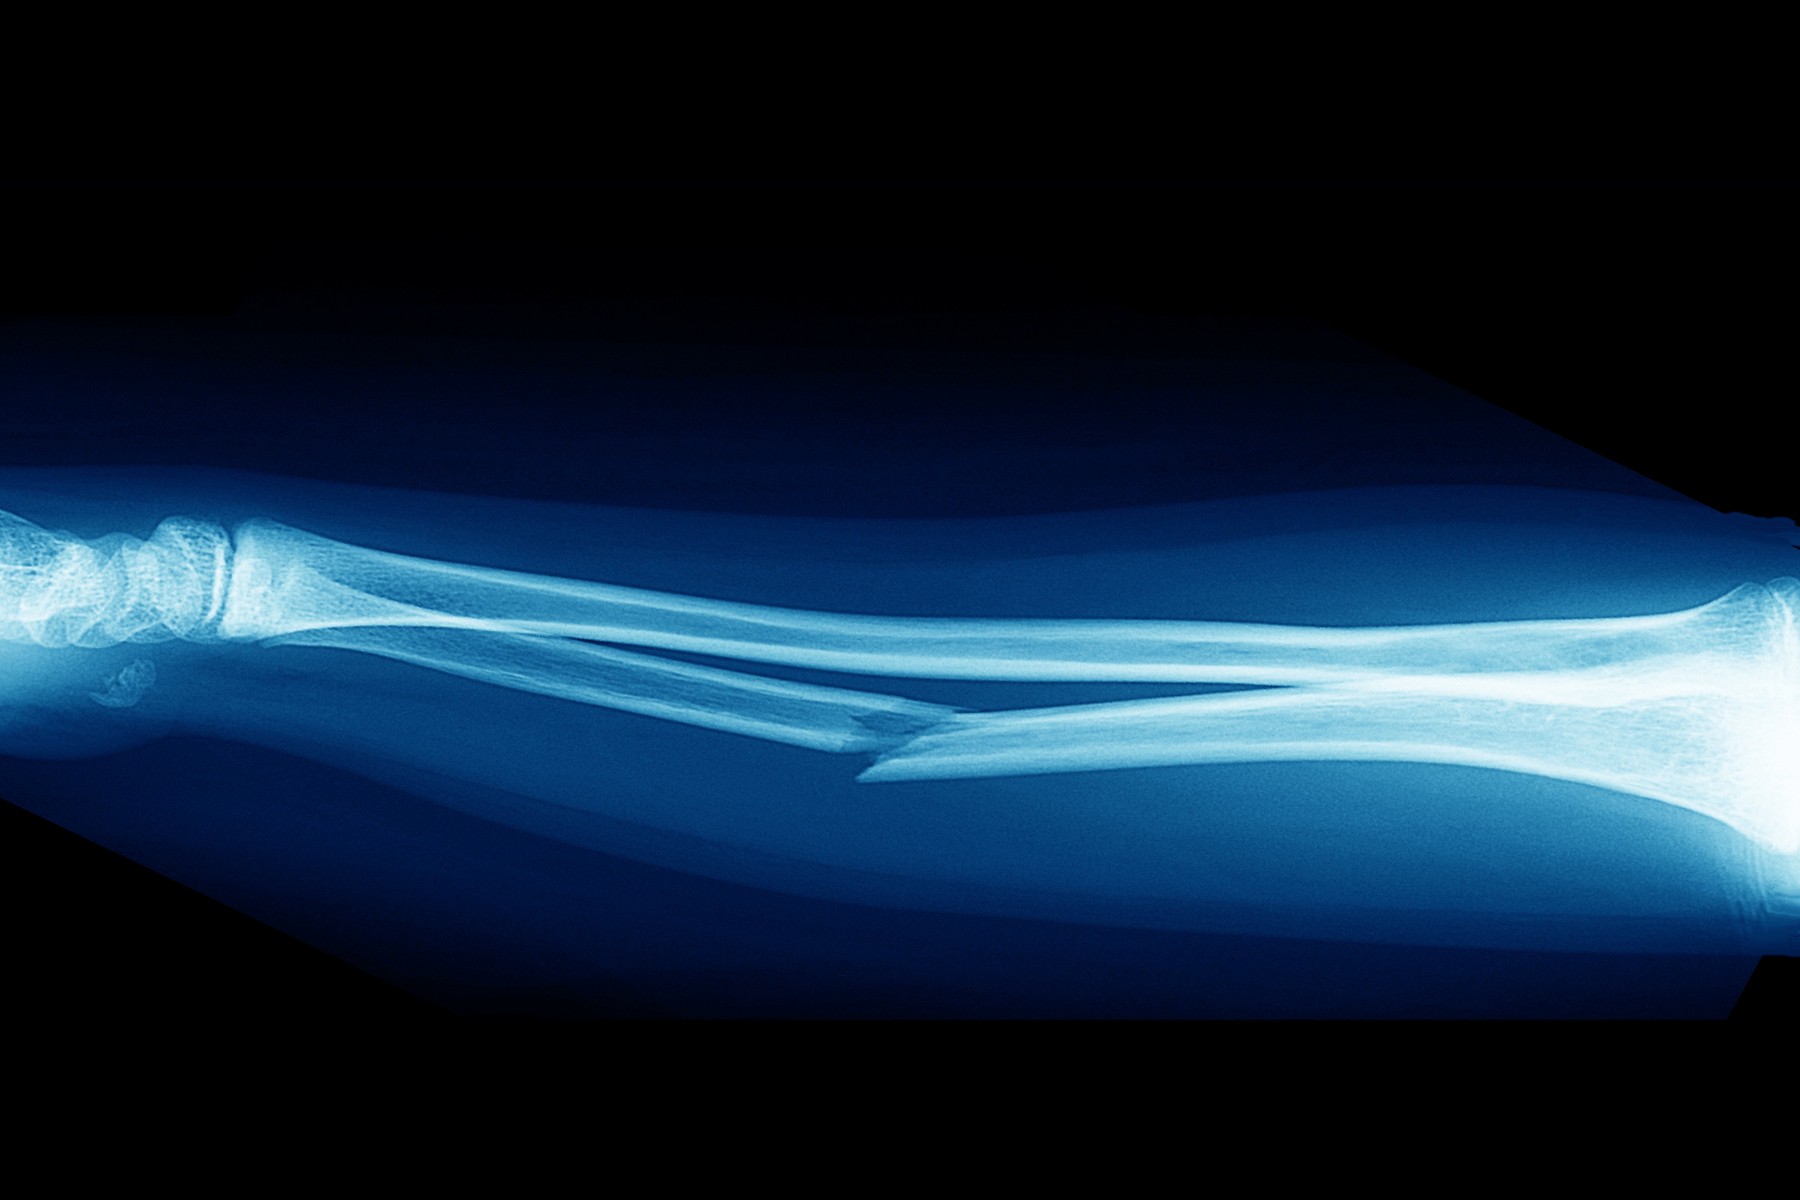

Nízkoenergetická zlomenina

Zvláštní pozornost věnuje osteoporóze u pacientů s chronickým onemocněním ledvin a u nemocných s hematologickými chorobami. Podílí se také na rozvoji konceptu Fracture Liaison Service, jehož cílem je systematická péče o pacienty po nízkotraumatických zlomeninách a prevence dalších fraktur. Ve výzkumu se zabývá vztahem metabolických poruch, hormonální regulace a kvality kostní tkáně. Osteologii chápe jako mezioborovou disciplínu, která propojuje interní medicínu, endokrinologii a prevenci závažných komplikací spojených se zlomeninami.